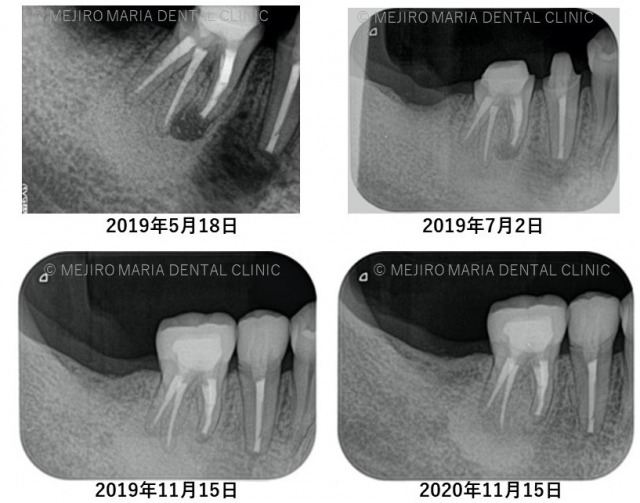

また、手術直後のレントゲン写真から比較すると、術後3ヶ月のレントゲン写真では順調に骨が作られていることが確認できる。

右下5番6番の透過像(黒い影)は2019年11月の経過観察時に消失し、その後安定していることがレントゲン写真より確認できる。